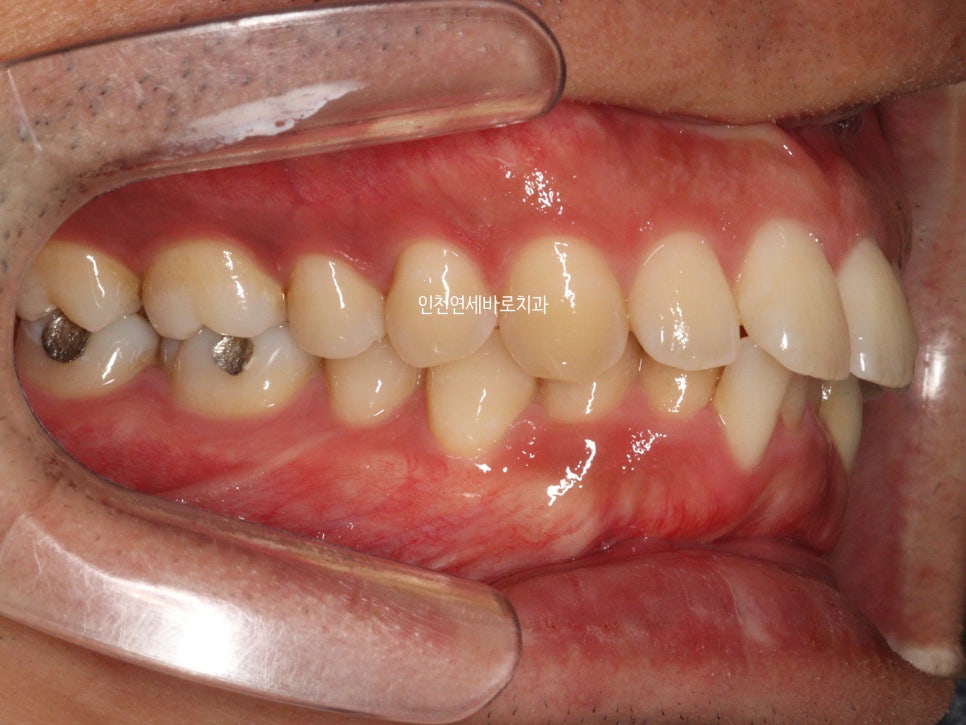

치료 전과 후의 비교입니다.

1회의 재제작.

각 제작마다 1달의 시간 소요

실질 치료기간 약 1년입니다.

교합도 양호하게 마무리.